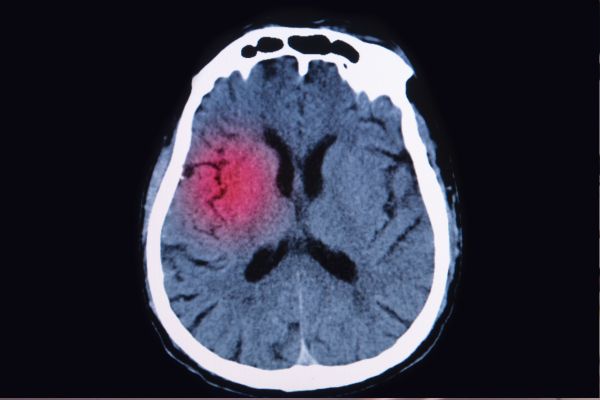

La urgencia de tratar un aneurisma cerebral roto

Cuando un aneurisma cerebral se rompe, se requiere atención médica inmediata. Los aneurismas rotos pueden tener consecuencias devastadoras debido al sangrado cerebral, lo que puede llevar a complicaciones graves o la muerte. «Generalmente, cuando tratamos a un paciente con un aneurisma roto, lo hacemos lo más rápido posible, normalmente dentro de unas pocas horas, ya que existe el riesgo de que el aneurisma vuelva a romperse», indica el Dr. Fox.